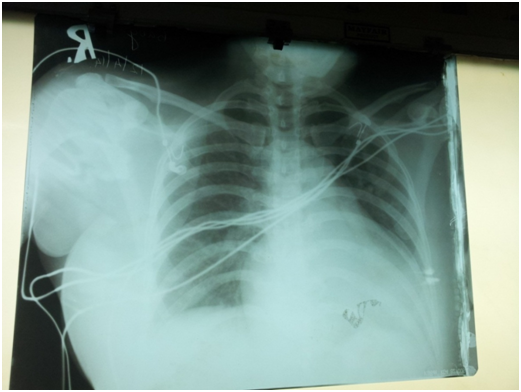

Her echocardiographic findings before supplementing calcium. Her LVIDD/S-5.2/4.5cms and IVSD/S-1.2/2 pwd/s-1.0/1.2 her ejection fraction was -26%. Her aorta/la dimension was 4/2.8.On treatment she improved .But on repeat echo she was found to have an left ventricular apical clot but her ejection fraction improved to 48 % (Figure 3).

Figure 3 The x-ray chest PA view of the patient when she first presented.

Gardner et al.,22 have described the ECG changes in both hypocalcaemia and Hypercalcemia. Hypocalcaemia causes on lengthening of the QT segment or QT prolongation they also report that those with a corrected QTc of more than 500 msecs have an increased chance of arrhythmias (Figure 4) (Figure 5). Various authors have also described hypocalcaemic cardiomyopathy in different cases that reversed with treatment.23–26

Figure 4 The gradually improving left ventricular function of the patient on correcting the QT interval , and her left ventricular apical clot.